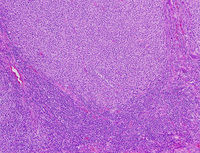

H&E images of LBCL with IRF4 rearrangement

Low power images show expanded nodules/follicles arranged back to back with attenuated mantle zones, replacing the normal architecture of the tonsil. At medium and high power, these nodules are composed of large atypical cells with moderate amounts of cytoplasm, mostly round to oval nuclei, finely clumped chromatin and basophilic nucleoli. Mitotic figures are not prominent and starry-sky pattern is not detected.